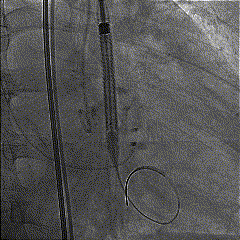

球囊预扩

TaurusElite输送系统柔顺过弓跨瓣后,AV26瓣膜瓣环平面定位释放,到工作位后造影瓣膜形态、位置良好,冠脉血流灌注正常;完全释放后瓣膜形态、位置良好,微少量瓣周漏。

定位释放

释放到工作位评估